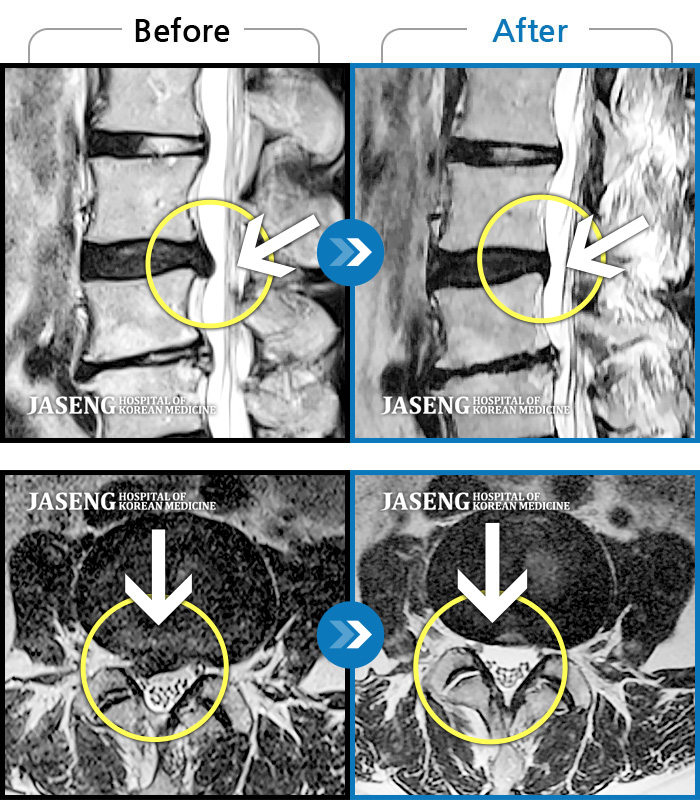

MRI 치료사례